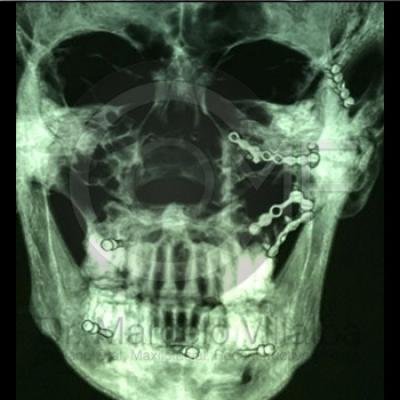

Fractura de Malar

Fractura De Malar16 Post